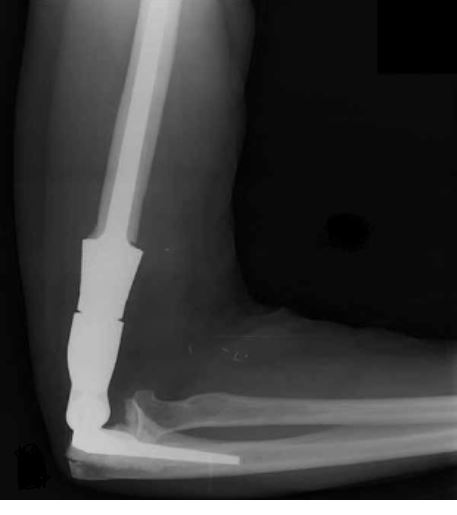

X-ray Photo

This is an X-ray image of the arm with the prosthesis.